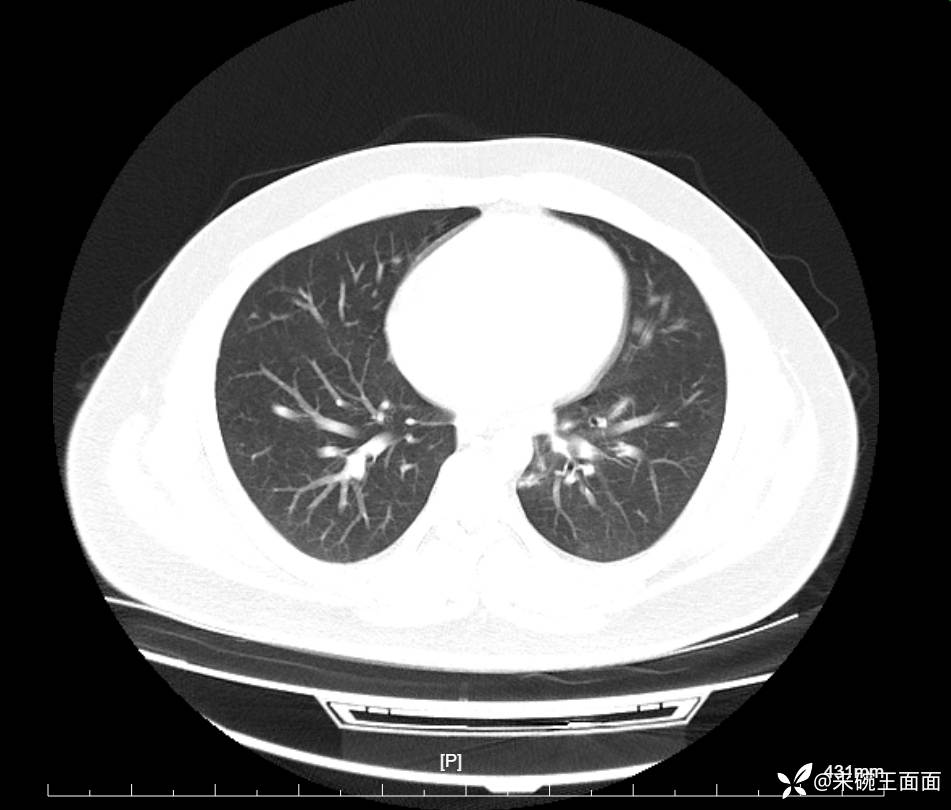

性别:男

年龄:27岁

主诉:胸闷胸痛数月余,休息后可自行缓解,无咯血症状。

个人史:数年吸烟史,具体不详。